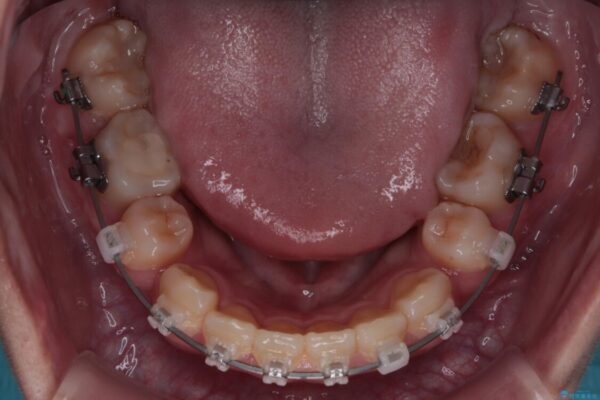

治療途中

• 転勤でも安心して治療継続 抜歯スペース閉鎖と深い噛み合わせ改善のワイヤー矯正 治療途中画像